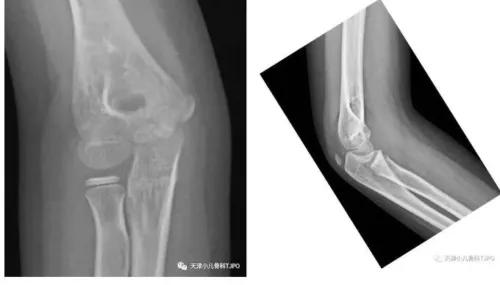

8岁6月,男,从单杠摔下肘上轻度肿胀压痛; X 线示 :正位未见明显异常,侧位可见帆船征。